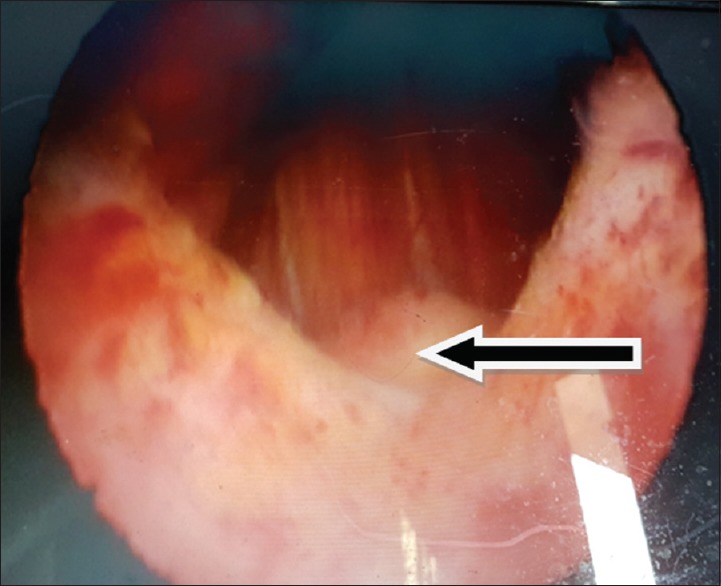

A 34-year-old civil servant presented to our facility, following a referral from a gynecologist who was also seeing the wife. The man presented with a history of anejaculation and the inability to impregnate his wife after 23 months of marriage. History, physical examination, and ancillary investigation led to a diagnosis of primary infertility secondary to posterior urethral valve which was subsequently ablated. Three weeks after ablation, he started ejaculating, and 2 months later, the wife became pregnant.

Abstract Image